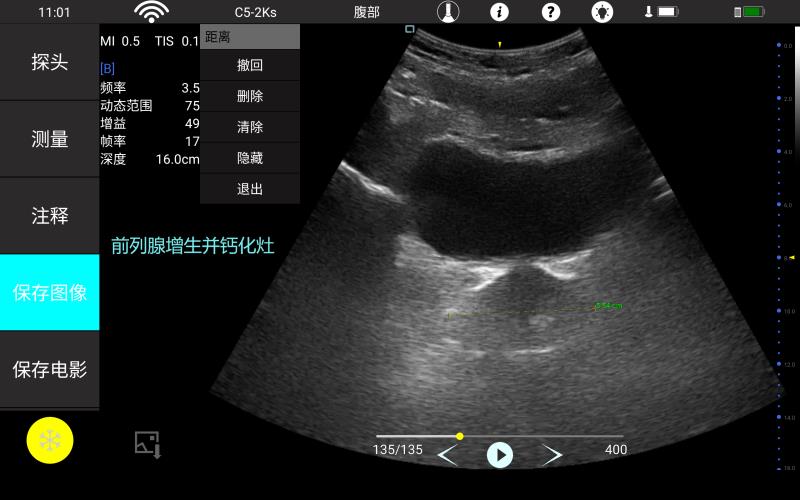

• 大凸

腹部

肾脏

妇科产科

心脏

肺等